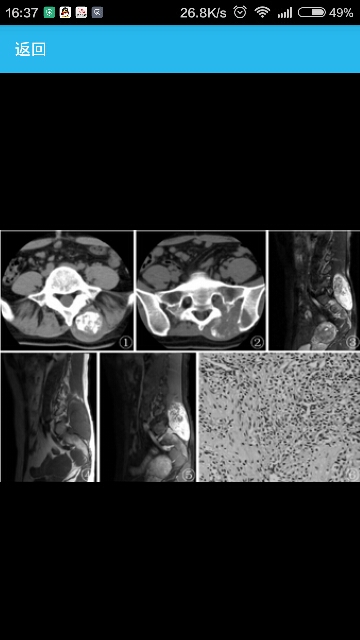

患者 女,34岁。临床表现腰部疼痛7年,左下肢放射痛2年,行走时疼痛加重,无寒战发热,无恶心呕吐,无外伤史。

辅助检查CT平扫示:左侧竖脊肌内见一类梭形软组织肿块,大小约41.04mm×41.10mm×83.68mm,边缘欠光整,内见点片状、块状钙化,左侧骶髂关节间隙及左侧髂骨受侵犯。MRI示:平扫左侧竖脊肌肿大,内见梭形肿块影,T1WI呈等、稍低混杂信号影,T2WI+FS呈等、低、高混杂信号影,且肿块内见多发颗粒状团片状无信号影,左侧髂骨内见片状高信号影。增强后病灶呈明显不均匀强化改变。

病理诊断:左侧竖脊肌骨外间叶性软骨肉瘤(图1~6)。